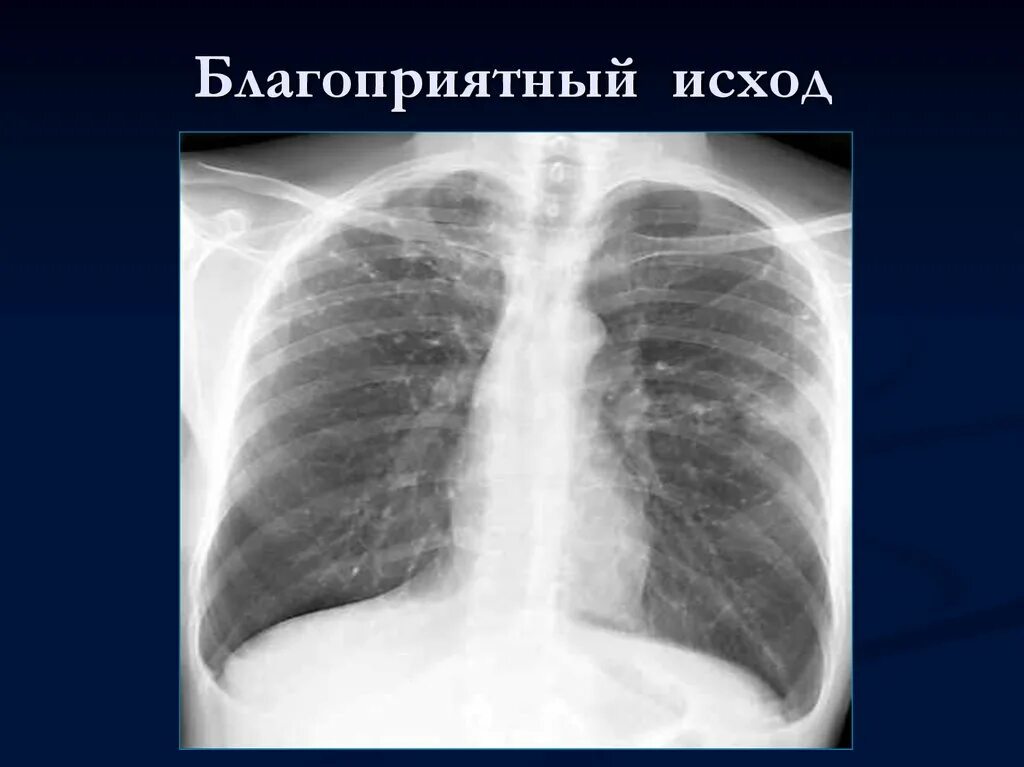

Бронхоаденит это